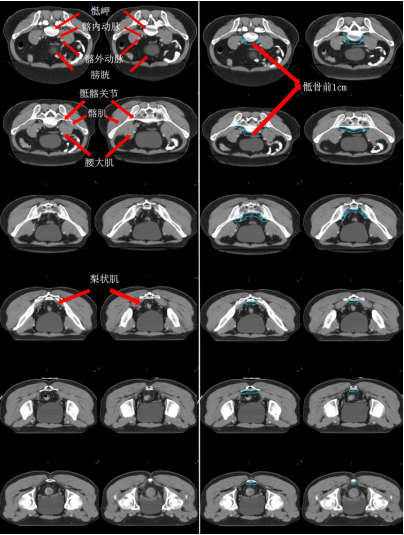

GTV 及 GTVnd 勾畫定義

a) GTV(紅色)通過對比定位 MR 圖像,在 CT 定位圖像完成 GTV 的勾畫(圖 1)。

圖 1 直腸癌 GTV 勾畫示例

a) 骶前區:分為腹部骶前區和盆腔骶前區

腹部骶前區-PS S (青色) (圖 5),邊界:

上界:腹主動脈分叉為左、右髂總動脈處或該區域內轉移淋巴結上方至少 0.5 cm;

下界:骶岬;

前界:腰椎前方 1 cm,髂總血管前 1.0 cm;

后界:腰椎前緣;

外界:髂總血管外側外 0.7~1.0 cm。

盆腔骶前區-PS (淡藍色) (圖 6),邊界:

上界:髂總動脈分叉為髂內、外動脈處/骶岬;

下界:肛提肌插入外括約肌處/直腸周圍系膜脂肪組織消失處,相當于尾骨尖水平;

前界:腰椎前方 1.0 cm/骶骨尾骨前方 1 cm/直腸系膜筋膜后緣;

后界:腰椎前緣/骶骨尾骨前緣;

外界:骶髂關節/髂肌內緣。

圖 5 直腸癌腹部骶前區 CTV 勾畫示例

圖 6 直腸癌盆腔骶前區 CTV 勾畫示例